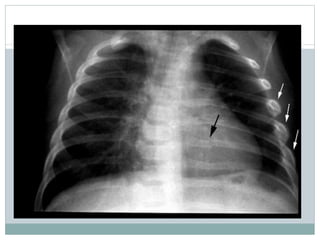

Ambos raio x’s muito rotados e descentralizados, tirado em pé

O que é e o que aconteceu ?

No 1° raio x ve se uma opacidade muito denso de quase todo pulmão direito com

desvio do mediastino para esquerdo, nao se ve linha de Alis/ Damoissau, o

limite é concav, provavelmente devido ha uma aderencia da pleura.

No 2° raio X ve-se um dreno, e agora ve-se infiltrado heterogenico nos 2 terços

inferiores do lado direito, um engrossamento da pleura direita (inferior) e falta

de tecido pulmonar que corresponde a um pneumotorax.